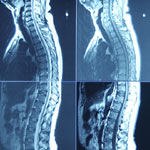

שברי חוליות נחלקים באופן גס לשני סוגים יציבים וכאלה שאינם יציבים. יציבם משמע שאין סכנה שיגרם נזק לחוט השדרה במהלך תקופת הריפוי . השבר עצמו מתאחה תוך פרק זמן של מספר שבועות והבעיה העיקרית היא לטפל בכאב. במקרים רבים ניתן לחזור לפעילות מלאה בתום תקופת הריפוי הראשונית. שברי לא יציבים הנם בעיה מורכבת יותר ויש סוגם שונים. הסווג הראשוני הנו ביןשברי םלאיציבים שאין לידם פגיעה עצבית ומנגד כאלו שבזמן ארוע השבר נגרם נזק למערכת העצבים. במקרה של שבר לא יציב ללא פגיעה עצבית צריך לדאוג ליצב את השבר עד שיתאחה. במקרה של שבר לא יציב עם פגיעה עצבית צריך ללמוד אם ניתן לגרום למניעת נזק נוסף או אף לתקן נזק קודם על ידי שחרור מלחץ ( מה שאומר ניתוח ) או שיש להסתפק בקיבוע למניעת נזק נוסף . היצוב של שבר לא יציב יכול להתבצע על ידי תקופת שכיבה ואחר כך קיבוע במחוך גבס או מחוך פלסטי . דרך אחרת היא בניתוח. איני יכול להתייחס לשבר של אחותך שכן אין לי עליו ולו גם שמץ של מידע

נראה שיש שבר בחוליה ושינויים ניווניים. בכל מקרה אין זה תחליף ליעוץ פרונטאלי.